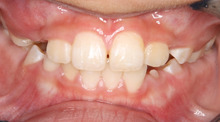

前から見ると

はっきりわかりませんが、

下の写真の矢印の部分の隙間に

大きな犬歯が生えなければいけません。

お母さんの心配通り、隙間はありません。

このままだと 八重歯になります。